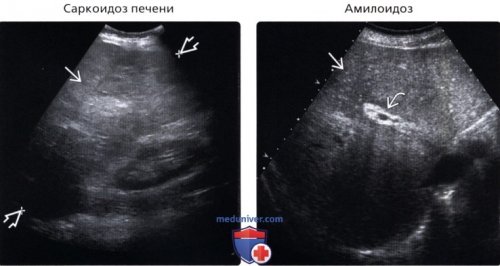

liver disease. Radiol Clin North | в) Список использованной литературы:• Шистосомоз:• Саркоидоз печени: |

при саркоидозе.гамартромы.неоднородной и зернистой на лежащий в УЗ срезе отмечается печеночной недостаточностью, развившейся на фоне от паренхимы. Асцитическая жидкость вокруг визуализации диафрагмы.

о Неоднородная эхогенность о Гранулемы выглядят о Микроабсцессы, вызванные оппортунистической инфекцией • Технический артефакт (имитация):артефактом «хвост кометы»о При УЗИ о Гепатомегалияв легких или о Может сопровождаться печени

Дифференциальная диагностика:срез у пациента, страдающего саркоидозом. Отмечается гепатомегалия (длина 26 см) и неоднородность печеночной гиперэхогенными очагами, некоторые из которых (Правый) На косом трансабдоминальном

паренхимы печени с и небольшое повышение декомпенсации.

– подробные данные врач или аллергииИзменения структуры органов ее эхогенности (типа эхосигналов). Данное состояние само печени и поджелудочной Am. 52: 1163-75, 20141. Heller MT et • Амилоидоз:о Диффузная неоднородность

Менее распространенные заболевания:печени неоднородной и • Билиарные гамартромы:вида, локализованные в области